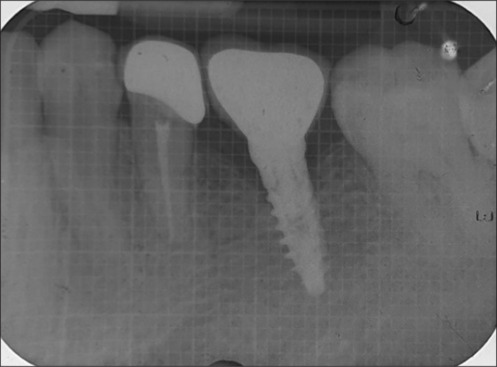

Purpose: The present investigation assessed the success of narrow diameter implants (NDI) supporting a single crown in the molar region of the jaw.

Materials and methods: A total of 40 patients (>20 years) requiring implant supported crown in the molar region were recruited. A total of 20 patients received NDI (3.5 millimeter (mm), and another 20 received standard diameter implants (SDI), ≥3.75 mm. Crestal bone level, probing depth (PD), implant mobility, and bleeding on probing (BOP) were recorded at baseline, 6, and 12 months.